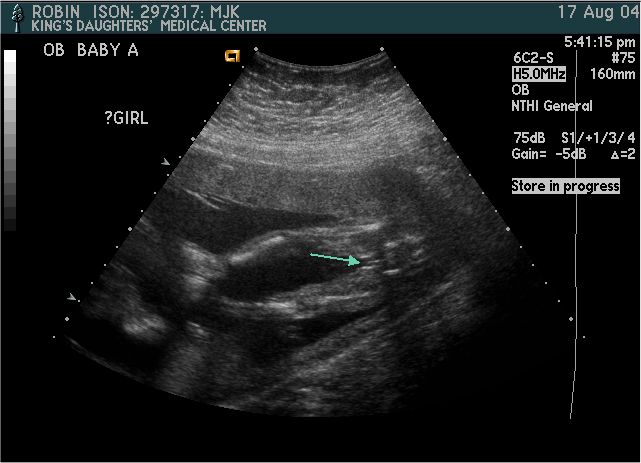

Baby A

Pictures from Ultrasound at 20 weeks.